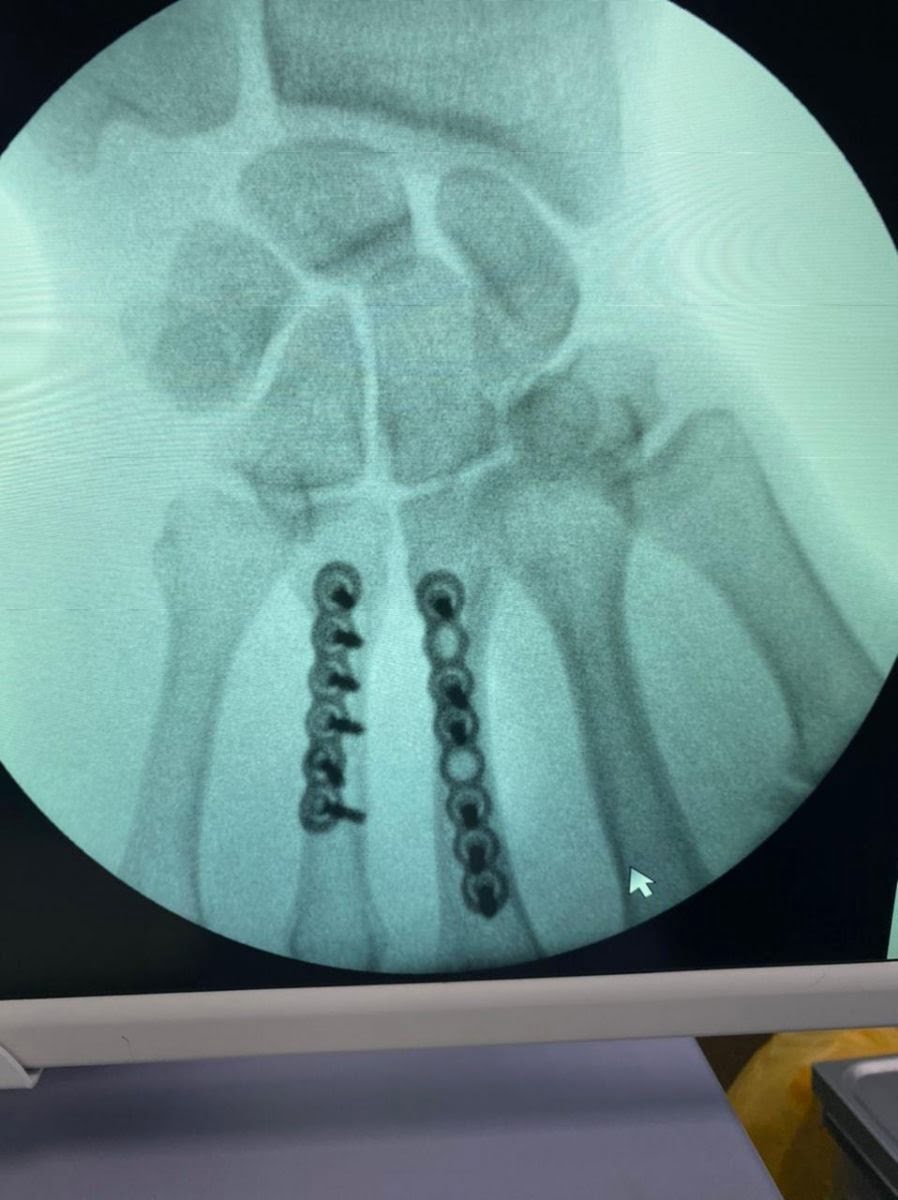

Наталья Непряева прооперирована в АНО ЦКБ Святителя Алексия Митрополита Московского, руководителем центра микрохирургии кисти, реконструктивной и пластической хирургии, к.м.н., доцент кафедры травматологии и ортопедии РНИМУ им. Пирогова - Калантырской Валентиной Анатольевной. Была выполнена реконструкция пястных костей 3 и 4 пальцев правой кисти при помощи специальных пластин. Сроки восстановления около 3-4 недель. После осмотра врача 1 февраля Наталья планирует свое возвращение в команду.